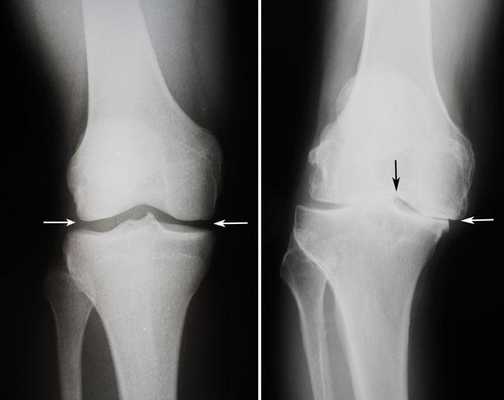

Артроз коленного сустава на рентгене.

Посмотрите на рентген, на нем вы видите, до какой степени при запущенном гонартрозе изношен гиалиновый хрящ, обеспечивающий гладкое скольжение суставных поверхностей. Концевые участки костей грубо деформируются нарушая функции сгибания и разгибания конечности вызывая интенсивный болевой синдром.

Сравнение здорового и пораженного сустава.

Динамика болезни на рентгене.